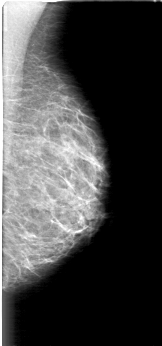

D_4037_1.LEFT_MLO

LEFT_MLO LINES 5176 PIXELS_PER_LINE 2416 BITS_PER_PIXEL 12 RESOLUTION 43.5 NON_OVERLAY